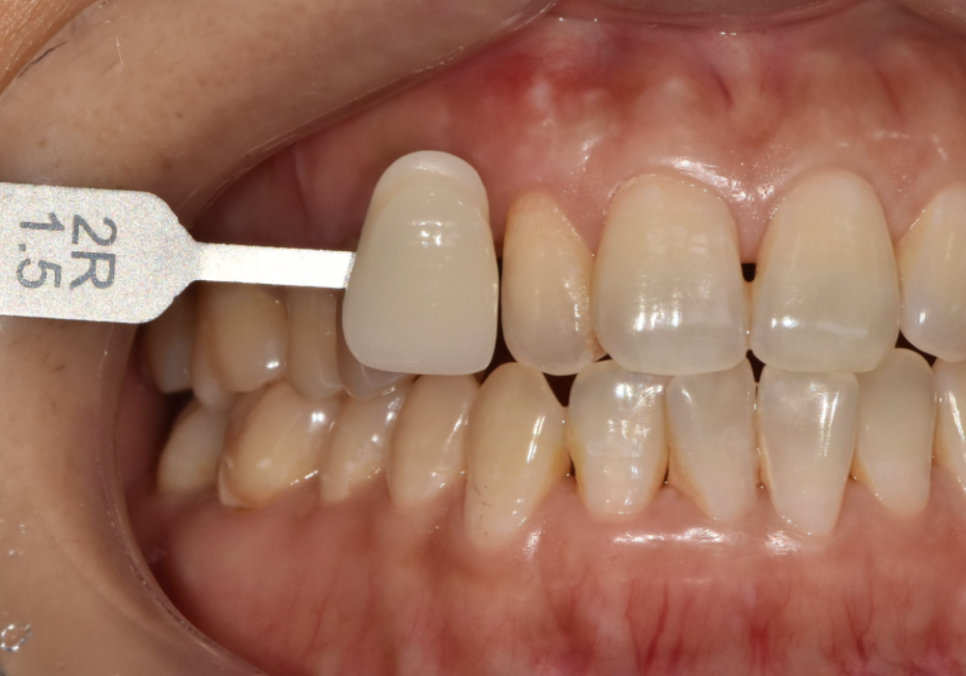

마지막 보철물(치아 머리) 제작에 들어갔습니다.

260224

그런데...여기서 한 가지 문제가 있었습니다.

원래 유치가 있던 자리라,

영구치 송곳니가 들어가기엔

공간이 꽤 좁았거든요.

자칫하면 치아가 혼자 너무 작고

왜소해 보일 수 있는 상황이었지만..

치아의 곡선과 잇몸 라인을

아주 세밀하게 조정해서

정면에서 봤을 때 최대한 자연스러워 보이도록

디자인에 공을 많이 들였습니다.

이런 정교한 작업이 가능했던 건

'원내 기공소' 덕분이었는데요.

외부 기공소에 맡기는 게 아니라,

저와 기공소장님이 실시간으로 소통하며

제작한 덕분에

환자분에게 딱 맞는 보철물을

끼워드릴 수 있었어요~

결과적으로 실제 가로폭은 좁지만,

정면에서 보았을 때 ! 어떠세요?

그닥 작아보이지 않죠~

주변 치아와 자연스럽게 조화를 이뤄,

어색하지 않게 제작을 도와드렸습니다. ^^